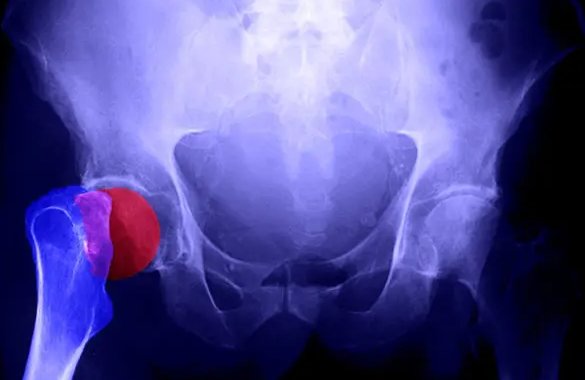

골다공증은 뼈의 밀도가 낮아져 쉽게 부러질 수 있는 상태를 말합니다. 이를 막기 위해 투여하는 골다공증 주사는 뼈의 손실을 늦추거나, 새로운 뼈 형성을 촉진하는 약제입니다. 보통 병원에서는 비스포스포네이트 계열 또는 파라티로이드 호르몬 유사체 등을 사용하며, 개인의 나이·성별·질병 경과에 따라 주사 종류와 투여 주기가 달라집니다.